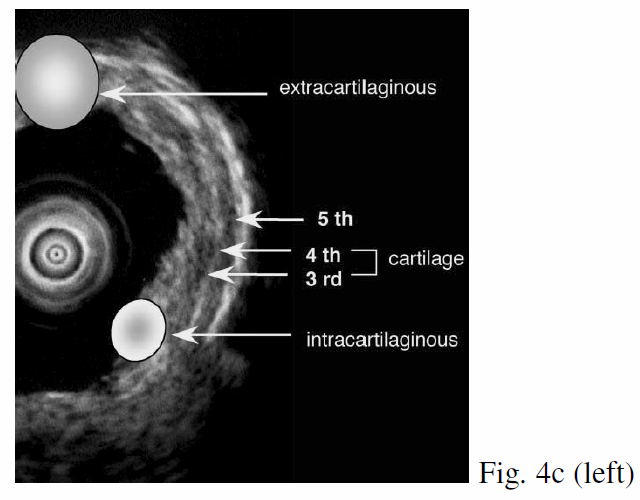

Seven echogenic layers of cartilaginous part and 3 echogenic layers of membranous part of tracheobronchial tree can normally be identified with R-EBUS (Fig 4a & 4b). The 3rd-5th layers denote the cartilage layers by which destruction determine invasion by central airway tumours (Fig 4c). Kurimoto et al. demonstrated that EBUS findings correlated well with histological findings in all 24 but 1 of cases, and the only false positive case was lymphocytic infiltration rather than tumour invasion of adventitia.3 Herth et al. also showed similar results in 56 patients. The false negative lesions were all located at the trachea. The small size of radial probe and the limited contact of balloon with tracheal wall could have been the reasons. EBUS findings were highly correlated with surgical findings (r=0.89, p<0.01), and with accuracy 94%, sensitivity 89%, specificity 100%, which compared favourably with CT (r=0.06, p=0.4), with accuracy 51%, sensitivity 75%, specificity 28% respectively.4